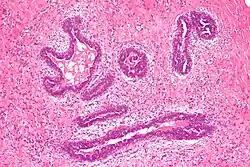

Histology

Early histological features expected to be seen on examination of gynecomastic tissue attained by fine-needle aspiration biopsy include the following: proliferation and lengthening of the ducts, an increase in connective tissue, an increase in inflammation, and swelling surrounding the ducts, and an increase in fibroblasts in the connective tissue.[26] Chronic gynecomastia may show different histological features such as increased connective tissue fibrosis, an increase in the number of ducts, less inflammation than in the acute stage of gynecomastia, increased subareolar fat, and hyalinization of the stroma.[24][26] When surgery is performed, the gland is routinely sent to the lab to confirm the presence of gynecomastia and to check for tumors under a microscope. The utility of pathologic examination of breast tissue removed from male adolescent gynecomastia patients has recently been questioned due to the rarity of breast cancer in this population.[57]